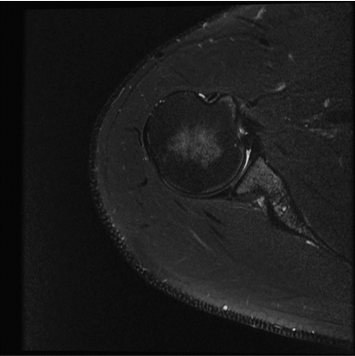

Conventional

384 x 256 (4 NEX)

3:00 minIAI (Innovative AI)

384 x 256 (2 NEX)

1:29 minscan time reduced up to 50%